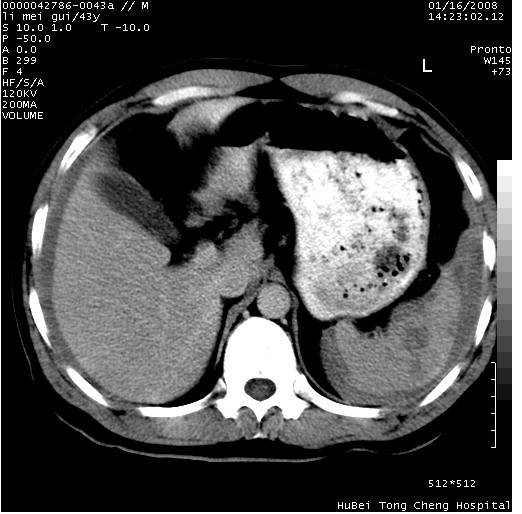

| 患者,男,43岁。突发腹痛2小时,面色苍白,难以平卧。自述近期无明确外伤史,为摩托车驾驶员。 腹部b超检查:脾脏中上极回声异常,肿瘤待排。 临床诊断:腹痛原因待查。 上中腹部ct轴位平扫+增强扫描(层厚10mm,螺距1.0,重建间隔10mm),图像如下: ![]() ![]() ![]() ![]() ![]() ![]() ![]() ![]() ![]() ![]() ![]() ![]() ![]() ![]() ![]() ![]() ![]() ![]() ![]() ![]() ![]() ![]() ![]() ![]() ![]() ![]() ![]() ![]() ![]() ![]() ![]() ![]() ![]() ![]() ![]() zrs发言:支持脾破裂 wwp发言:支持脾破裂并腹水。 xulianj发言:脾脏肿瘤破裂可能性大 zsl6918发言:不像肿瘤出血,考虑还是与外伤后引起的慢性出血有关 zzyy发言:平扫见肝周及脾周积液,脾内密度不均。脾内肿瘤较少见。还是外伤性脾破裂。 沈丘东方医院发言:脾门区一个不均匀强化病灶与其周液体相连多考虑脾占位破裂出血 yixianman001011发言:脾破裂并腹水是可以肯定的,具体原因多以肿瘤性破裂出血,脾脏淋巴瘤可能性大. 结果: 术后,经详细询问患者,其仔细回忆:一月前骑摩托时左侧腰部与别人有“轻微”触碰,因责任在自已,当时又无明显不适,未引起注意。 临床术后诊断:脾破裂并失血性休克(1.外伤性迟发性脾破裂。2.脾脏肿瘤破裂?) 术后标本病检:脾破裂并出血,未见明显肿瘤成份。 原贴地址:http://www.radinet.com.cn/forum_view.asp?forum_id=4&view_id=34070 |